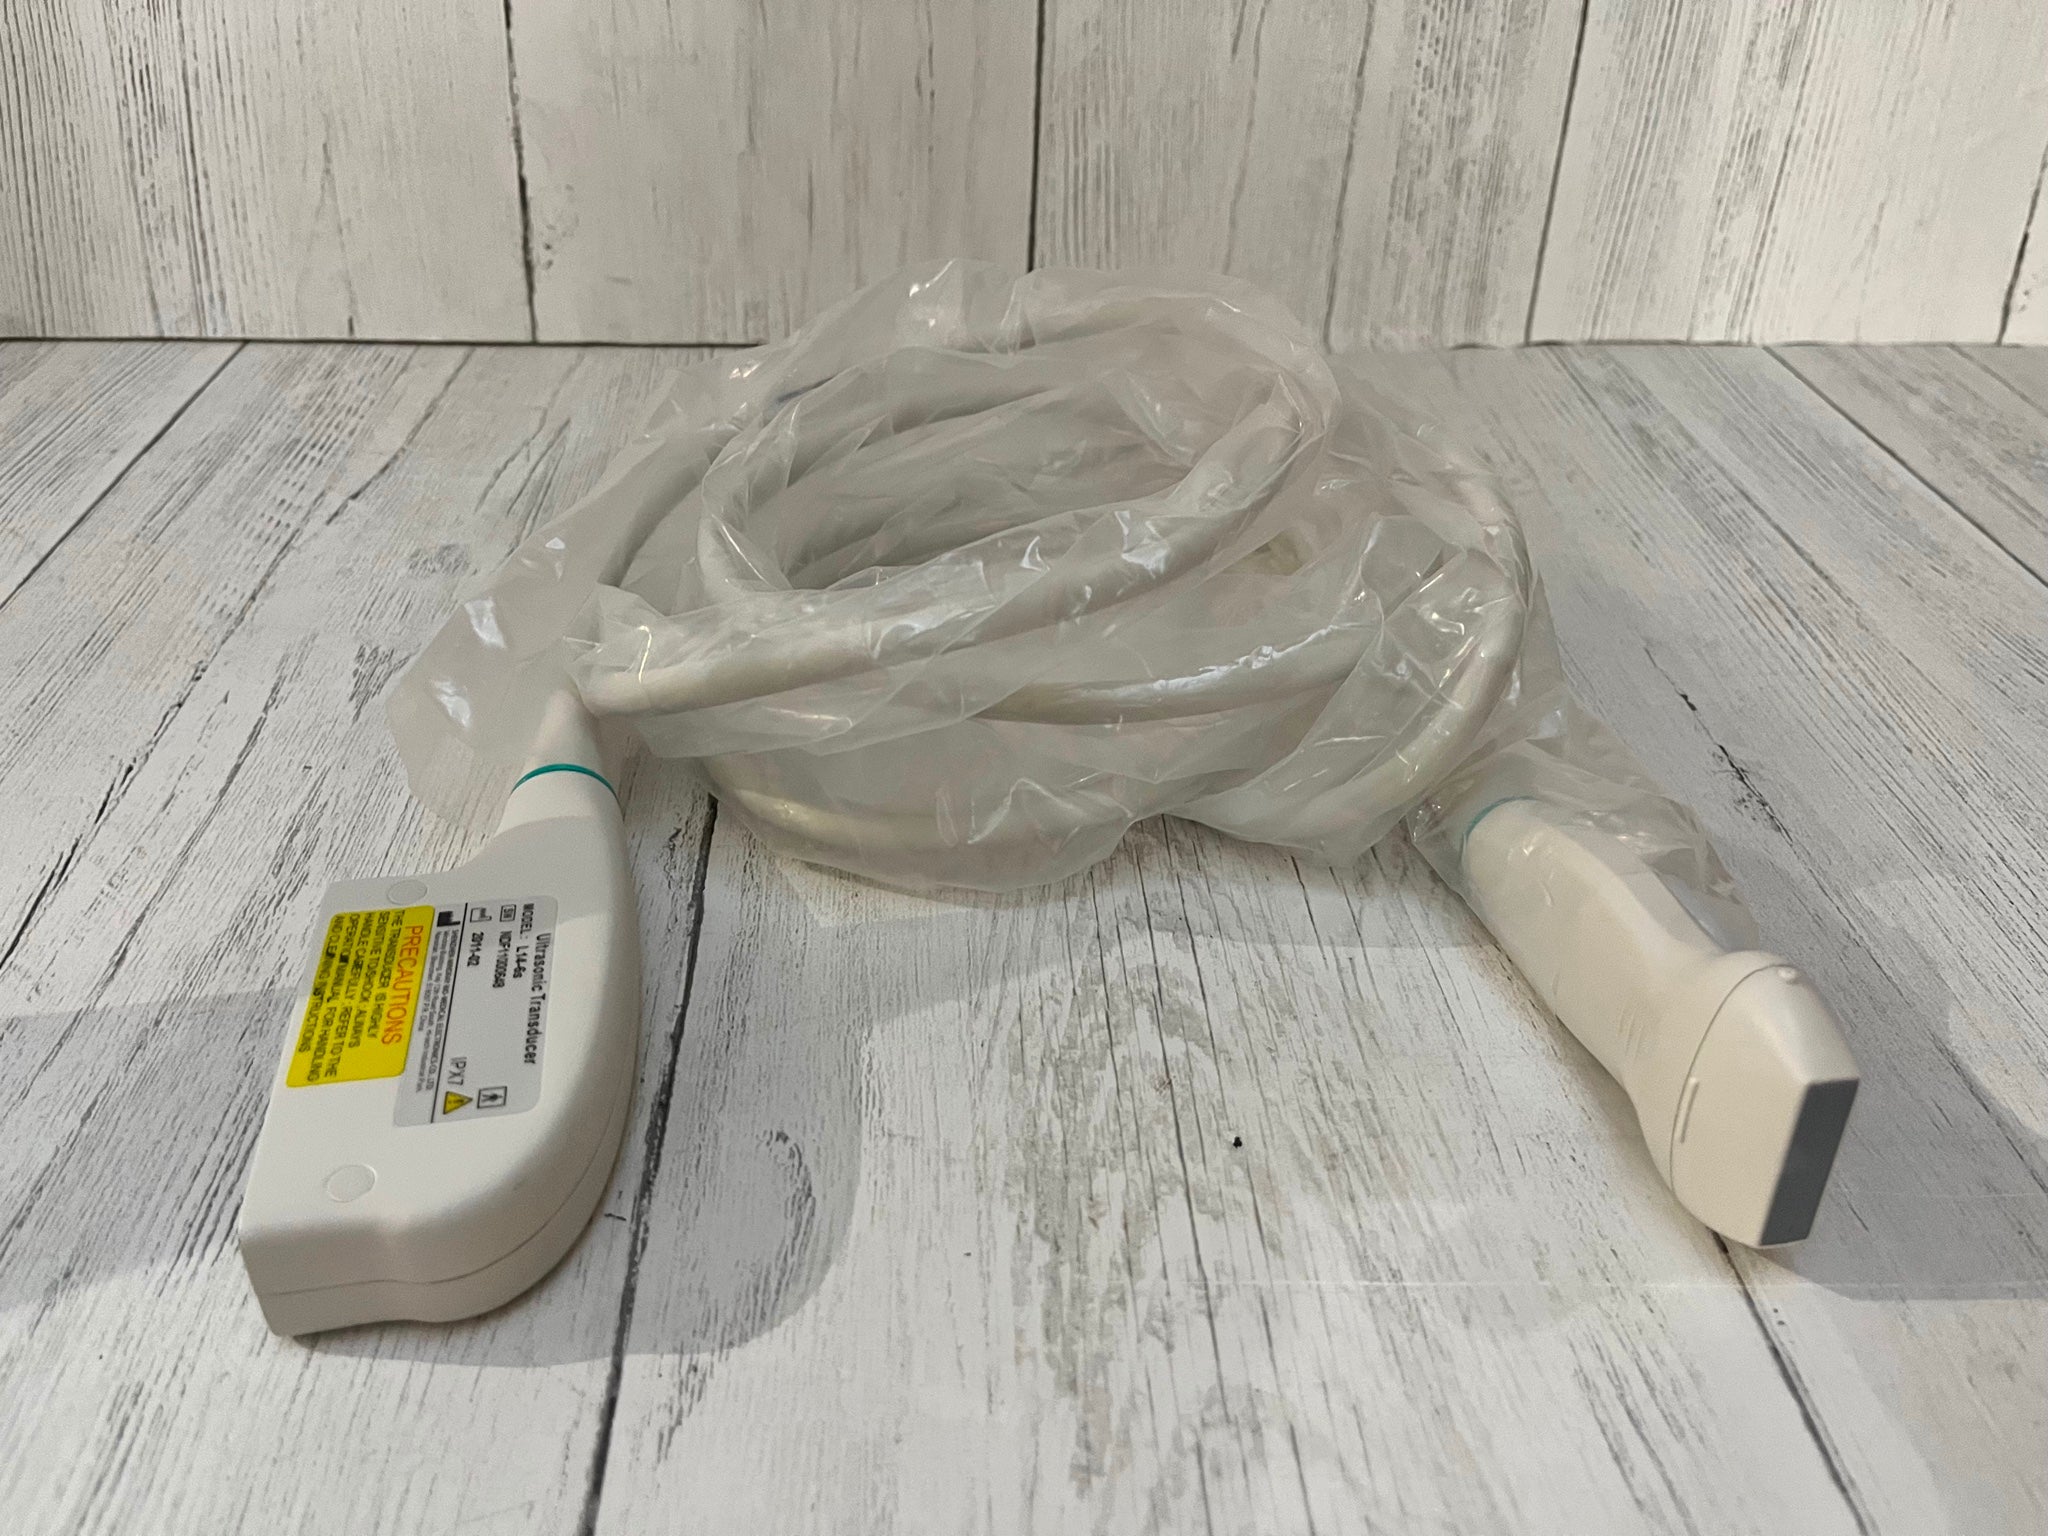

Probe Type

80 elements

Frequency

Convex array 2-5MHZ / Linear array 5-10MHZ

Standard Configuration

Main unit (Transducer included): 1pc,USB wire: 1pc

Adapter: 1pc Carrying bag: 1pc Bag of gel(20g): 1pc |